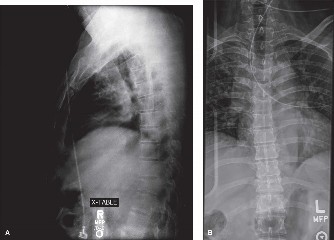

Radiographic follow-up includes upright AP and lateral plain films before discharge to verify the maintenance of sagittal alignment and hardware integrity. The patient is discharged home or to acute inpatient rehabilitation depending on their functional mobility.

Long-term follow-up at 6 weeks, 3 months, 6 months, and 1 year will focus on assessing fusion mass consolidation and monitoring for any signs of hardware failure. More importantly, long-term surveillance (2 to 5 years post-op) will focus on the adjacent segments. By having meticulously restored the sagittal vertical axis (SVA) and regional lordosis during the index procedure, we have minimized the abnormal shear and compressive forces on the T10-T11 and L3-L4 discs, drastically reducing the patient's risk of developing Adjacent Segment Degeneration requiring revision surgery.